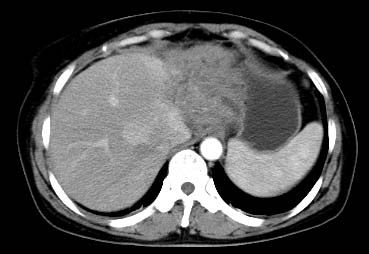

以下是引用西北一只狼在2008-6-30 20:58:00的发言:[br]肝左叶胆管细胞ca并肝门淋巴结转移、胰腺、胃小弯浸润

以下是引用ydx_74在2008-6-30 21:54:00的发言:[br]左叶胆管细胞ca并肝门淋巴结转移、胰腺、胃小弯浸润